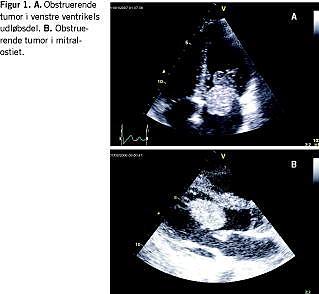

Patienten blev intuberet og direkt current (DC) blev flere gange konverteret på ventrikelflimmer (VF) til sinusrytme flere gange. Efter 45 minutters genoplivning blev der opnået sinusrytme, og man indledte hypotermibehandling. En ekkokardiografi i skadestuen viste en bredbaset tumor i venstre ventrikel på septum tæt ved udløbsdelen samt diffust nedsat kontraktilitet (Figur 1). Transøsofagal ekkokardiografi (TEE) og computertomografi støttede de ekkokardiografiske fund. Patienten var i de første døgn svært ustabil med gentagen VF og skridende uddrivningsfraktion (EF) til 10%. På grund af mistanke om svær anoksisk cerebral skade og primær mistanke om malignitet afstod man fra overflytning til et transplantationscenter. Ved en fornyet TEE blev der i venstre ventrikel påvist en enkelt 3,8 cm × 2,4 cm stor tumor med bevægelse mod udløbsdelen. Patienten klarede de følgende dage cerebralt helt op, var cirkulatorisk og respiratorisk stabil og normaliserede sin EF.

Ved en akut ekkokardiografisk undersøgelse blev det påvist en 4 cm × 7 cm stor tumor i venstre atrium. Tumoren var tilhæftet septum og pendulerede gennem mitralostiet (Figur 1 ). Hjertet var i øvrigt strukturelt normalt. Patienten blev stabiliseret og opereret et døgn senere. Ved torakotomi under ekstrakorporal cirkulation, eksstirperedes fra venstre atrium en 65 g stor tumor, adhærerede til septum. Mitralklappen var intakt. En frysemikroskopi og efterfølgende histologisk undersøgelse bekræftede myksomdiagnosen.